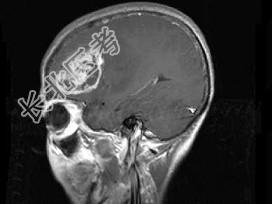

- 单项选择题女,52岁, 头痛伴呕吐2周,根据所提供图像, 最可能的诊断是 ( )

A、转移瘤

B、星形细胞瘤Ⅱ级

C、星形细胞瘤Ⅰ级

D、少枝胶质细胞瘤

E、脑脓肿